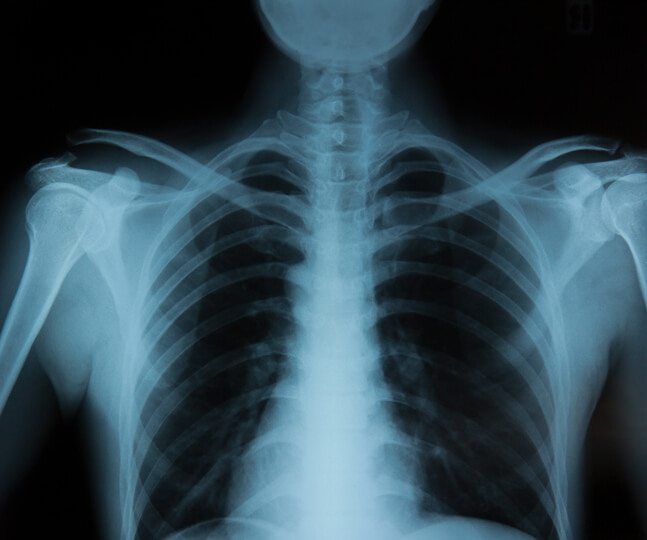

X-ray equipment is one of the most important when it comes to diagnostic video imaging medical equipment. This is because the device was the forerunner of all other technologies in this area, such as tomography, mammography, and magnetic resonance devices. But what was already good got even better. Today, radiological equipment is available in many types, sizes, and prices. So, if you are thinking of … Continue reading X-Ray Equipment: A Diagnostic Imaging Tool